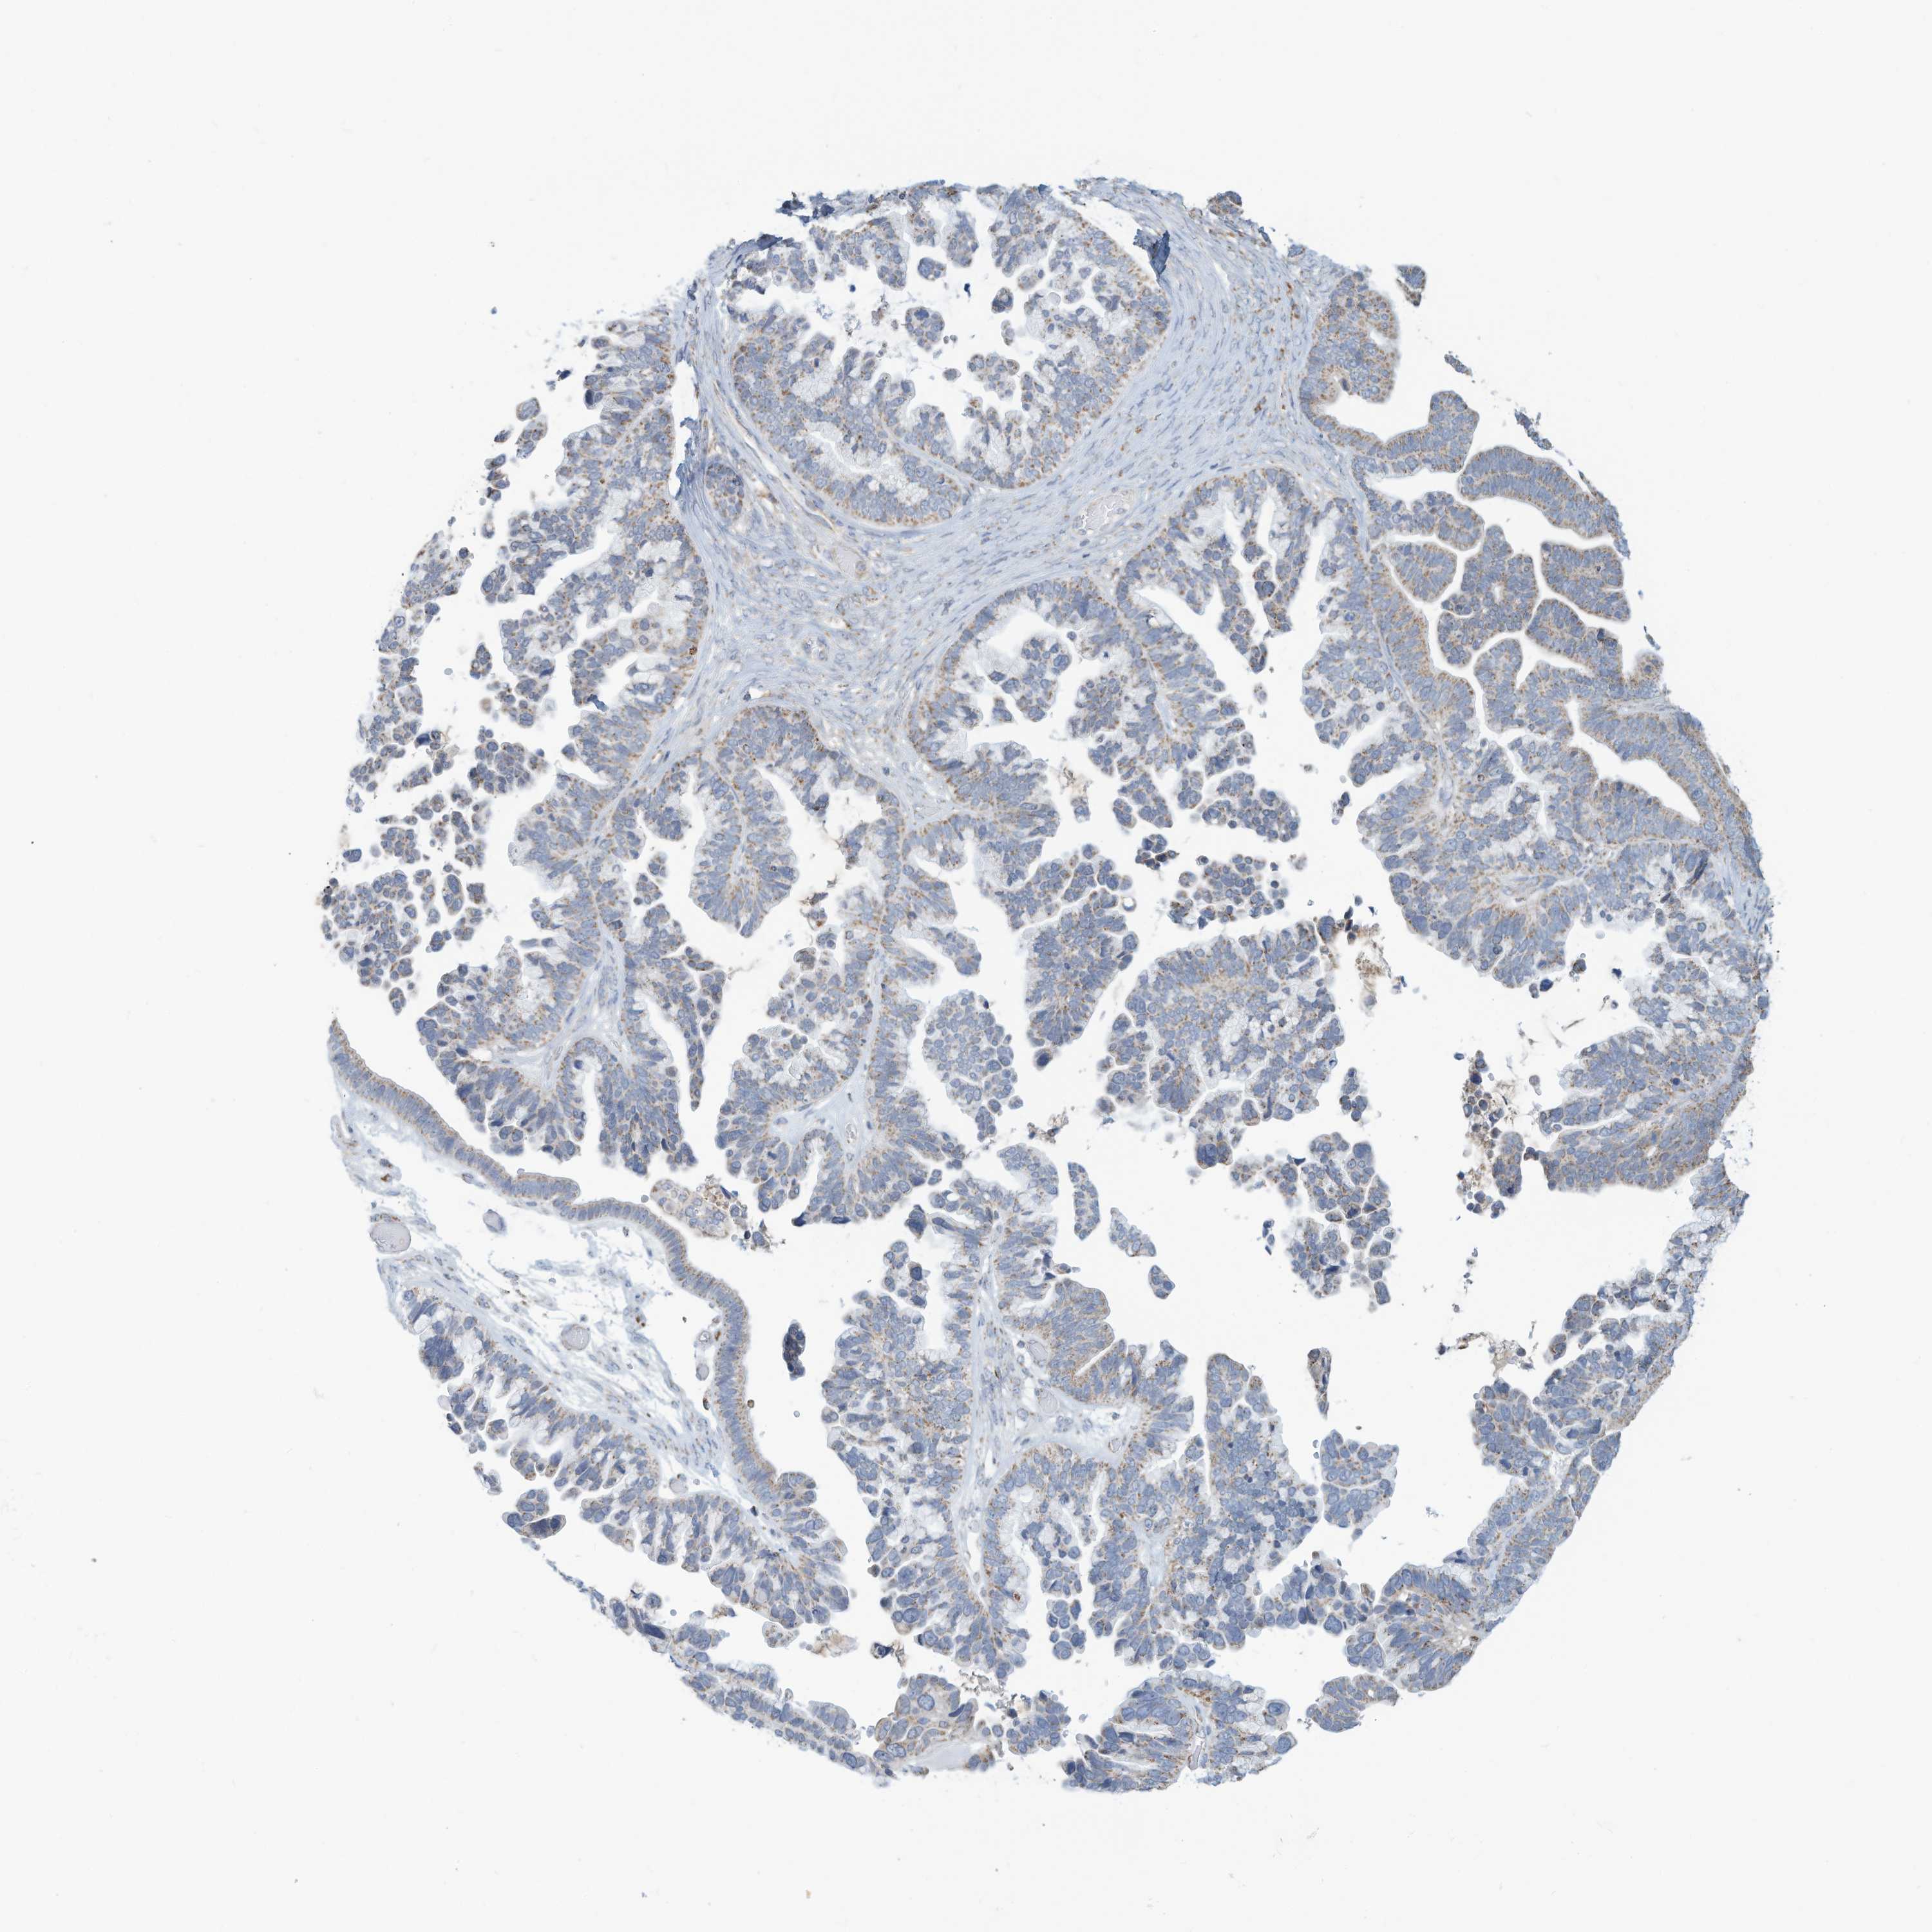

OVARIAN CANCER - Protein expressioni

A mouse-over function shows sample information and annotation data. Click on an image to view it in a full screen mode. Samples can be filtered based on level of antibody staining by selecting one or several of the following categories: high, medium, low and not detected. The assay and annotation is described here.

Note that samples used for immunohistochemistry by the Human Protein Atlas do not correspond to samples in the TCGA dataset.

Antibody stainingi

Antibody staining in the annotated cell types in the current human tissue is reported as not detected, low, medium, or high, based on conventional immunohistochemistry profiling in selected tissues. This score is based on the combination of the staining intensity and fraction of stained cells.

Each image is clickable and will lead to virtual microscopy that enables deeper exploration of all samples and also displays staining intensity scores, fraction scores and subcellular localization as well as patient and tissue information for each sample.

Antibody HPA031862

Staining

High

Medium

Low

Not detected

Intensity

Strong

Moderate

Weak

Negative

Quantity

>75%

75%-25%

<25%

None

Location

Nuclear

Cytoplasmic/membranous

Cytoplasmic/membranous,nuclear

Carcinoma, endometroid